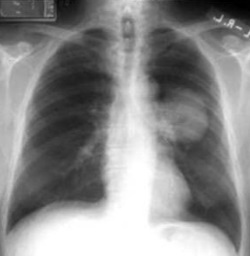

Q

¿Cuál es el dx?

A

Carcinoma broncogénico